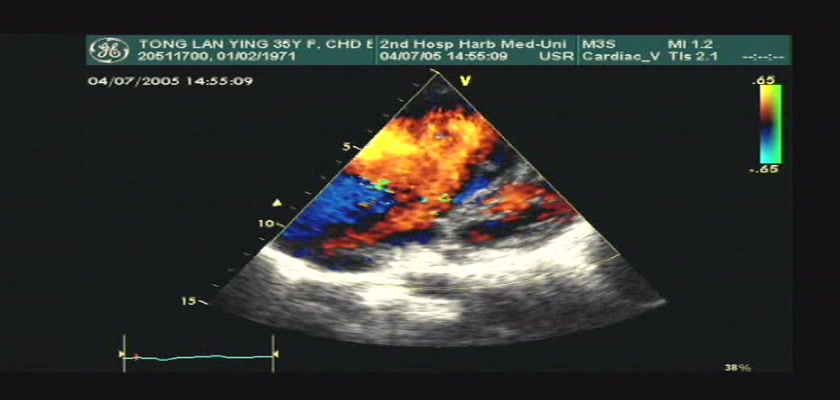

先天性心脏病超声诊断-先天性心脏病超声诊断视频19